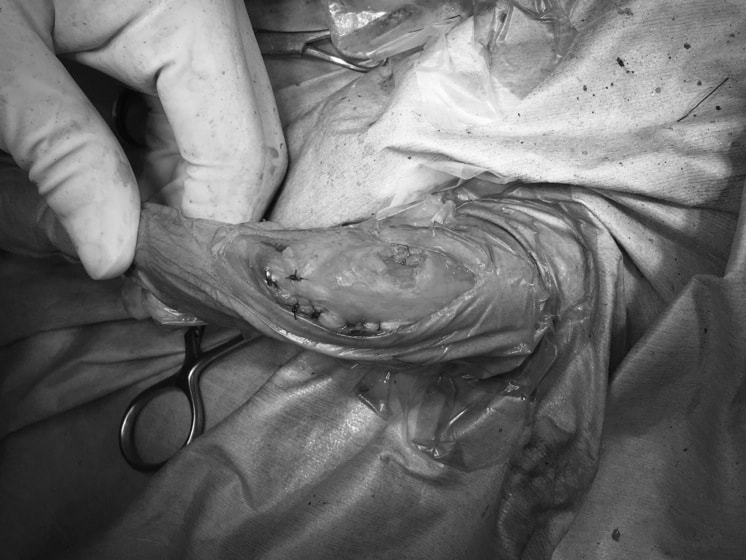

■ 症例20 ポメラニアン 8ヶ月 1.8kg

左右膝蓋骨脱臼 グレードⅢ

2ヶ月前から間欠的跛行が認められ、両膝の膝蓋骨脱臼整復術を行った。

手技は縫工筋及び内側広筋の解放、脛骨粗面の外側転位、滑車ブロック形造溝術、内外側関節包の縫縮を選択し実施した。

右側の膝蓋骨脱臼は上記手技で整復されたものの、左側はそれのみでは膝蓋骨が浮く様子が認められた。その為、PDS縫合糸にて膝蓋靱帯を1糸のみ縫合し、靱帯の縫縮を行った。

膝蓋骨脱臼は膝関節における膝蓋骨の内外側の脱臼と定義されるが、時として単純な内外の脱臼ではなく、膝蓋骨が大きく前方に浮き上がるように脱臼する場合がある。特にトイプードルやポメラニアンといった犬種に多く認められる。

内側脱臼に加えて前方への浮き上がりを矯正する為に、従来より脛骨粗面転移により膝蓋靭帯を外方と下方に引っ張り、固定する方法を選択する。膝蓋骨の前方への浮き上がりが軽度の場合は、従来法ではなく関節包の縫縮で対応していた。しかし、一部の症例で膝蓋骨の動きが悪くなり伸展機構が円滑に機能せずロボット様歩行になるケースがあった。

その為、膝蓋靭帯自体を縫縮する方法を採用した。この方法により、膝関節の伸展機構を妨げず膝蓋骨の軽度の浮きを矯正することが可能となった。

本症例の経過は良好である